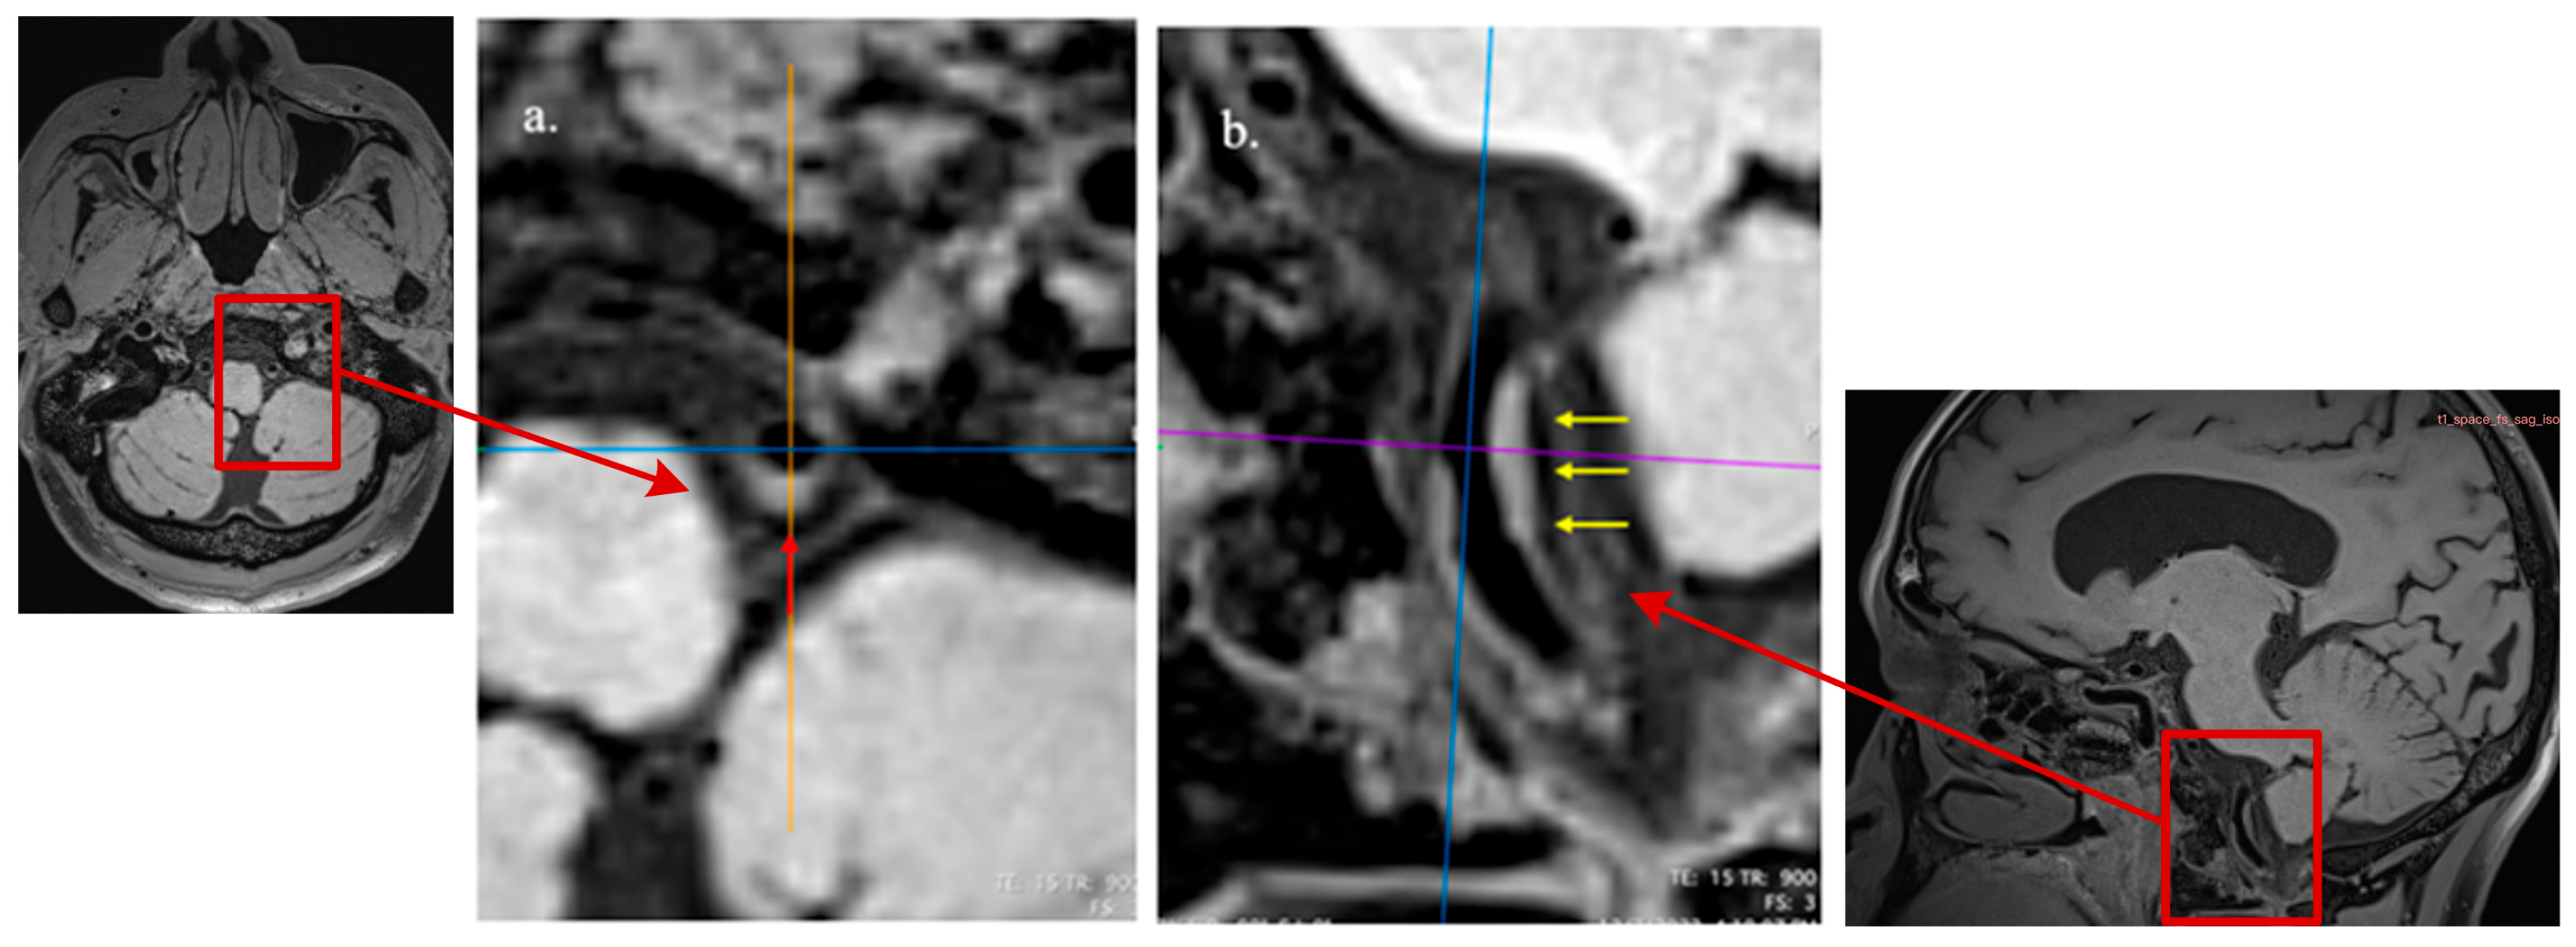

Among 272 participants, 102 (37.5%) showed abnormal electrical activity waveforms with a mean heart rate of 72.2 ± 10.4 bpm. Participants with ICAS were more likely to have atrial myocardium oxygen deficiency impairment when compared to those without ICAS (70.2% vs. 57.5%, p = 0.030). Figure 4 indicates the physiological functional status of the myocardium in different cardiac segments using a gradated color-coded image on ECG dispersion mapping. Based on the time-domain SDNN of overall HRV, irregular changes in heartbeat were detected in 94 cases, of which 60 (39.7%) also had ICAS, compared to 28.3% participants without ICAS (p = 0.040) (Table 2).

Figure 4. The physiological functional status of the myocardium in different cardiac segments using a color-coded ECG dispersion map. Green indicates a healthy state, as shown in (a); yellow represents the normal upper limit, and red indicates myocardial ischemic injury. (b) indicates local hypoxia occurring in the left atrial myocardium (the area is shown by an elliptical red outline).